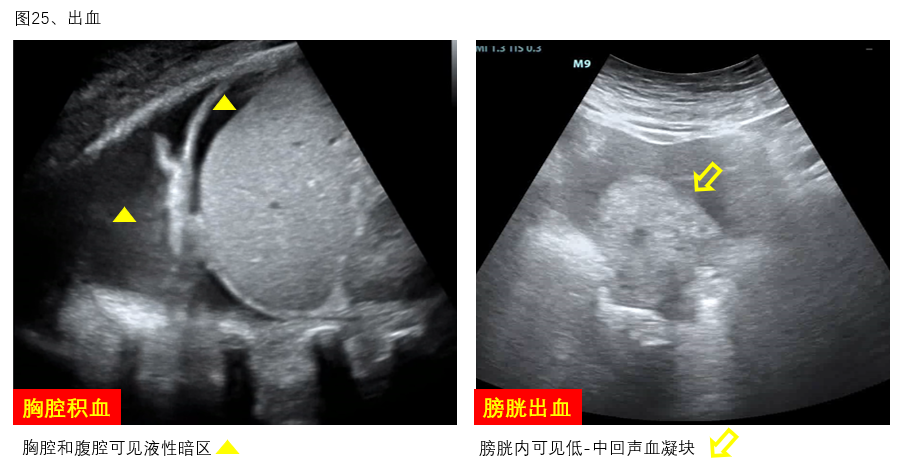

9、出血:出血是ECMO患者常见的并发症,床旁超声可通过直接或间接超声证据协助判断出血部位、血肿范围、对周围组织器官压迫情况等(图25)。明确出血部位和出血量可为抗凝强度调整提供参考,此外,超声还可以协助积血定位和穿刺引流。

图25